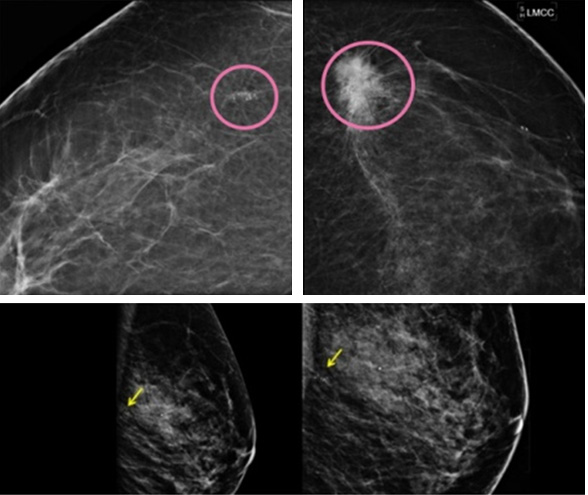

확대압박유방촬영술 (Magnification-Compression Mammography)

조기유방암의 표지가 될 수 있는 미세석회화를 보는데 가장 정확하고 좋은 검사법입니다.

미세석회화는 가는 소금을 뿌려 놓은 듯 하얀 점으로 유방촬영사진에서 나타나는데, 워낙 작아서 유방영상의학과 전문의들은 돋보기를 이용해서 판독합니다.

암의 표지로 석회화의 크기, 모양, 분포가 무엇보다도 중요합니다.

유방사진상 미세석회화가 보이면 정확한 진단을 위해서 반드시 확대압박촬영술을 실시해야 하고 여기서 암이 조금이라도 의심되면 위치를 확인하여 조직검사를 하게 됩니다.